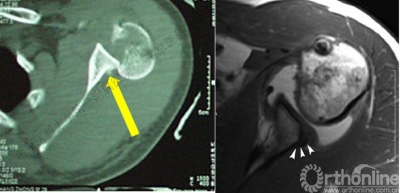

2.肩关节CT

确定肩关节后脱位。

了解反Hill-sachs损伤和程度。

观察肱骨近端主要骨折线和次要骨折线及形态。

3.肩关节MRI

了解肩胛盂、肩袖及周围软性结构损伤情况。